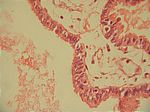

Extrauterine Gravidität Tube, HE